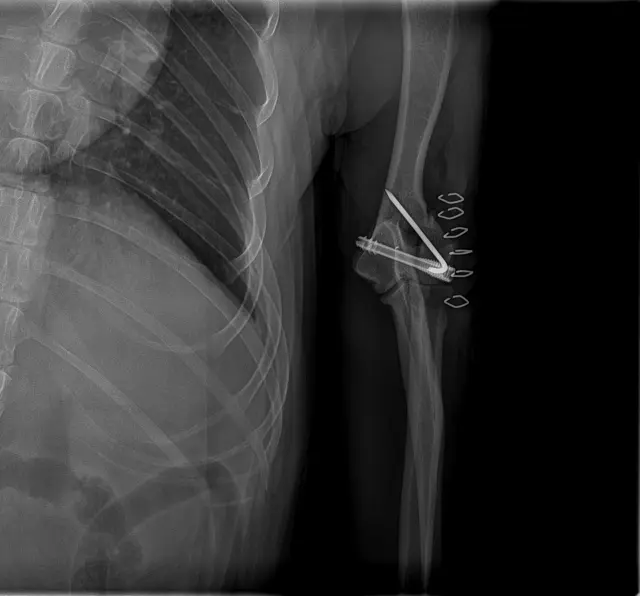

Bruno si v sobotu při nešťastném pohybu vážně poranil pravou přední nohu. Na pohotovosti u MVDr. Tesaře byla diagnostikována dislokovaná fraktura laterálního epikondylu humeru – jedná se o bolestivou zlomeninu, která mu znemožňuje pohyb a způsobuje velké utrpení.

Operaci musí provést specialista MVDr. Adam Hylák z kliniky Vyvet ve Vyškově. Jedině chirurgický zákrok dává Brunovi naději, že se znovu postaví na nohy a dožije stáří bez bolesti.